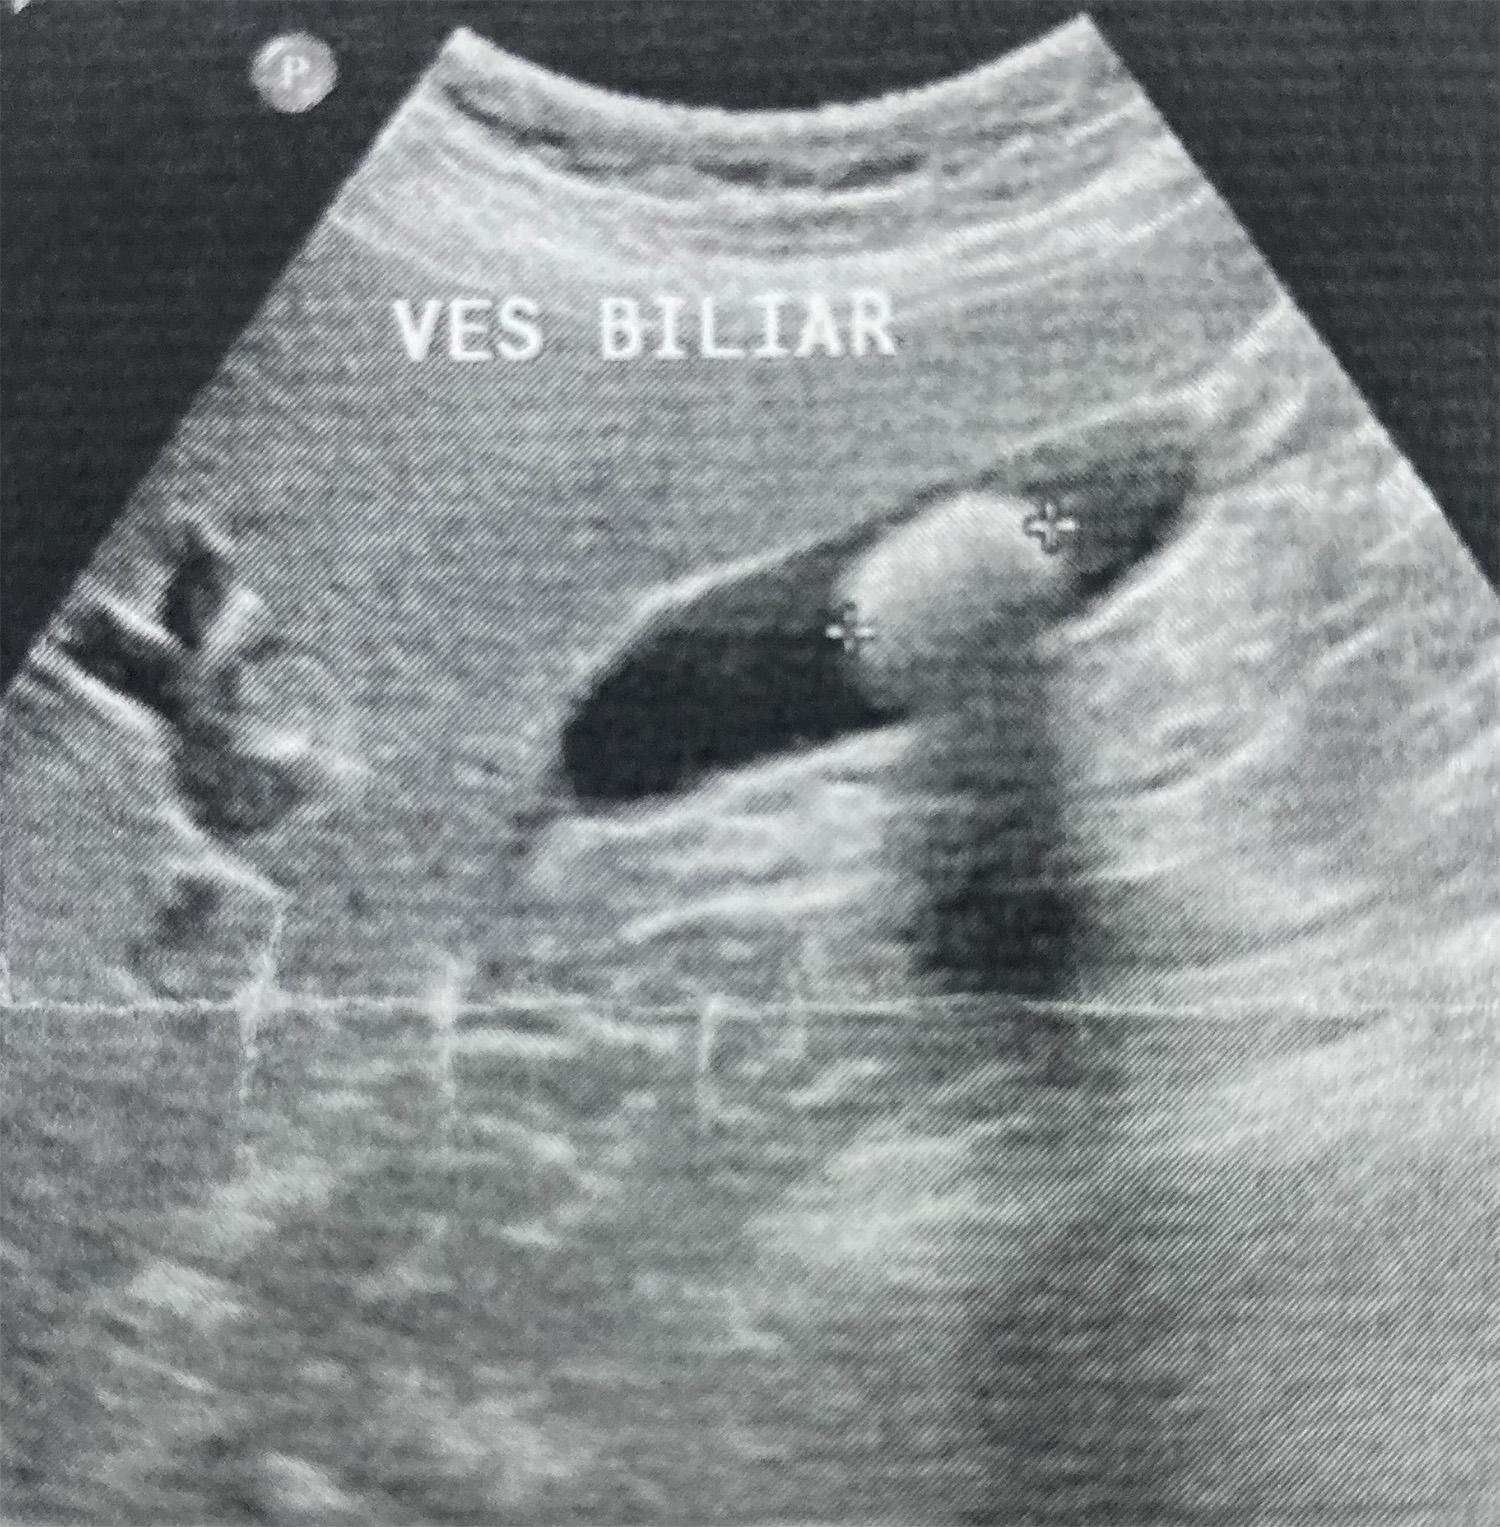

Colelitíase

Caso Código 253A de Colelitíase - Case Code 253A of Cholelithiasis

Ultrasson revelando colelitíase com cálculo único, e sombra acústica posterior.